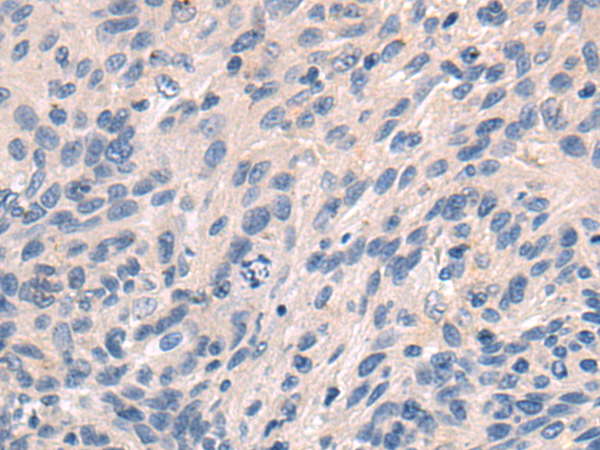

分类: 科研抗体货号: P13786别名: NUMA; NMP-22应用: IHC反应种属: Human, Mouse